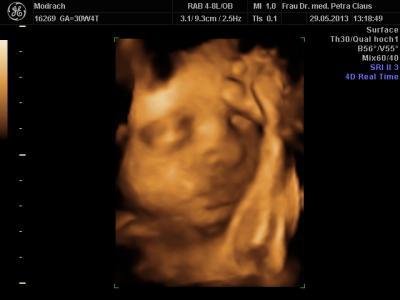

Erstmal was schönes, der Zwerg liegt in schädellage und wiegt bei 32/0 ca 1900 g mit 42 cm:) Dann war ich ja letzten Freitag in der Klinik und dort hieß es erst 4 cm zervix mit Zyste im Muttermund. Die wäre auch nicht schlimm, so etwas kommt vor, dann hat sie den schallkopf anders gehalten und meinte doch großer Trichter mit Fruchtblasenvorwölbung und 1,3 cm. Heute war ich bei meiner ambulanten gyn. Sie war sich auch nicht sicher. Tendiert aber mehr zu den Zysten, weil es wohl zystische Strukturen wären und der gmh 5 cm. Das wär ja Top. Oder Vll 1,5 cm mit großen Trichter. Von der fruchtblase hat sie nichts gesagt. Naja toll, keiner legt sich fest. Nun soll ich weiterhin Bettruhe halten, um auf Nummer sicher zu gehen. Und in der Klinik meinten sie 2te lungenreife und meine Ärztin kennt nur 1 x lungenreife. Das ist alles ziemlich verwirrend. Hatte jmd mal so etwas? Lg